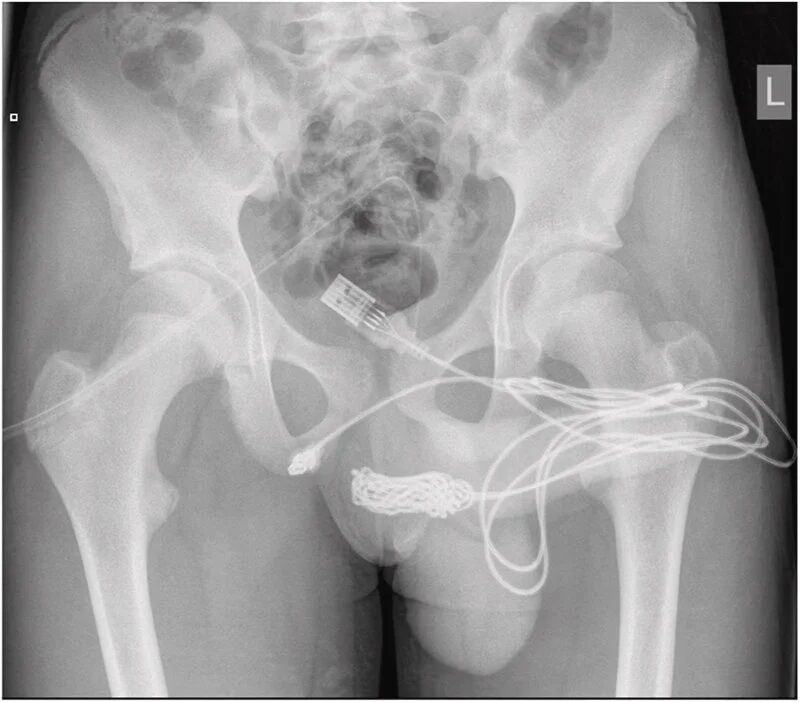

その後、緊急で同病院に搬送された。この時、ケーブルの2つの端が尿道口から飛び出していた。結び目は尿道内に留まったままだった。

手術では、球海綿体筋を開き、結び目を取り出して切断。ケーブルの残りは尿道から抜き取られた。

公開された画像からは、摘出されたUSBケーブルの大きな結び目が確認できる。